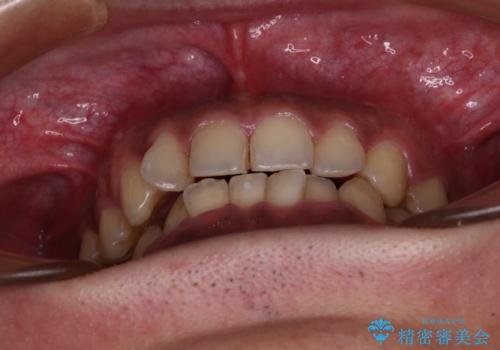

- 前歯のデコボコを気にして来院された患者様です。

前歯が90度近く捻れていたため、しっかりと治すことを考えるとワイヤー矯正の方がおすすめではありましたが、本人の希望によりインビザラインを用いて矯正治療を行うこととしました。

途中2年強の来院がなく、改善されていたデコボコが元に戻ったり、装着時間が不足しており前歯のデコボコは十分に改善することはできませんでしたが、5年間の有効期限内で可能な限り歯列を整えることができました。